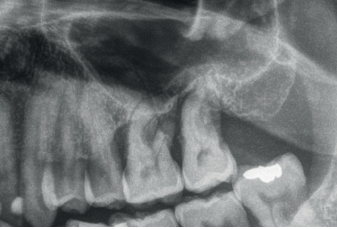

Todos los pacientes fueron tratados por un mismo cirujano, para la realización de la inserción de los implantes y la técnica de elevación transcrestal. Antes de la inserción de los implantes se utilizó una premedicación antibiótica consistente en amoxicilina 2gr vía oral una hora antes de la intervención y paracetamol 1 gramo vía oral (como analgésico). Posteriormente los pacientes prosiguieron con un tratamiento de amoxicilina 500-750 mg vía oral cada 8 horas (según peso) durante 5 días. Todos los pacientes fueron estudiados antes de la inserción de los implantes mediante modelos diagnósticos, exploración intraoral y realización de una tomografía computerizada de haz cónico (CBCT), analizado posteriormente mediante un software específico (BTI-Scan III). La cirugía se lleva a cabo mediante la técnica de fresado biológico descrita por nuestro grupo de estudio previamente, a bajas revoluciones, sin irrigación10, hasta ser finalmente completada mediante la elevación transcrestal con las fresas de corte frontal que se emplean también a bajas revoluciones. Una vez la membrana es accesible mediante la perforación crestal se despega mediante una ligera presión y se inserta el implante con el motor quirúrgico fijado a 25 Ncm y 25 rpm finalizando la inserción del implante con la llave dinamométrica. Todo el hueso recogido con las fresas se conserva en PRGF-Endoret fracción 2 sin activar, para posteriormente ser utilizado como injerto óseo particulado en la elevación, sin otros materiales accesorios9,12. Una vez finalizada la cirugía se realiza una radiografía periapical con paralelizador que será la que se utilice como punto de partida. Los pacientes acuden posteriormente para la realización de radiografías periapicales de control, tomadas con la misma técnica y sobre estas radiografías se realizan las mediciones necesarias para comprobar la estabilidad y pérdida ósea crestal de los implantes. La medición de la pérdida ósea marginal se realizó en la última radiografía periapical realizada con posicionador de seguimiento.

En la Figura 2 se muestran los diámetros y longitudes de los implantes incluidos en el estudio en función de los milímetros de cresta ósea residual en altura. La densitometría media de la zona de inserción del implante del grupo fue de 293,33 HU (+/- 144,99). El torque medio de los implantes estudiados fue de 27,33 Ncm (+/- 16,99). Todos los implantes se cargaron en dos fases quirúrgicas y en todos se llevó a cabo una elevación de seno transcrestal con injerto óseo autólogo particulado obtenido del fresado, embebido en PRGF-Endoret como marterial de injerto. En ninguno de los casos se registraron complicaciones relativas a la cirugía. Los implantes presentaron un seguimiento medio de 13,33 meses tras la carga (+/- 3,09), no encontrándose complicaciones ni fracasos durante este tiempo de seguimiento, por lo que la supervivencia fue del 100%. Todos los implantes fueron rehabilitados mediante prótesis múltiple atornillada mediante elemento intermedio (transepitelial múltiple, Multi-im®), encontrándose dos de los implantes ferulizados a otros de la misma longitud (4,5 mm) y el resto a longitudes mayores. La ratio corona-implante medio para el grupo de estudio fue de 2,43 mm (+/-0,45). La pérdida ósea mesial final media de todos los implantes fue de 0,42 mm (+/- 0,51) y la pérdida ósea distal final media de 0,16 mm (+/-0,34). En las Figuras 3 –13 se muestra uno de los casos incluidos en el estudio.